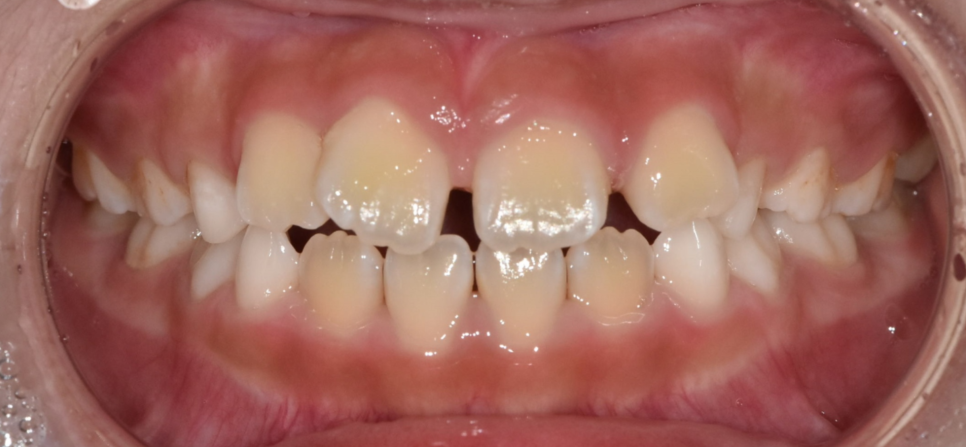

초등학교 1학년 아이의 치아입니다.

어린이 덧니로 인해

걱정이 되는 마음에 방문해주셨습니다.

250218

덧니는 미관상 좋지 않지만

충치나 잇몸질환의 위험이 증가합니다.

칫솔질이 어려워 그렇습니다.

250218 겹쳐지는 부위는 잘 안닦이겠죠?